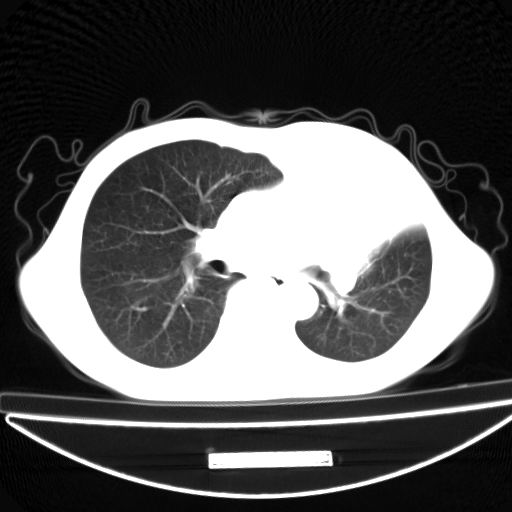

以下是引用杀毒软件在2009-4-28 17:58:00的发言:[br]考虑----左肺慢性肺脓肿形成继发上叶含气不良---抗炎后复查---待排肿瘤所致[br][br][本贴已被 杀毒软件 于 2009-4-28 18:01:26 修改过]